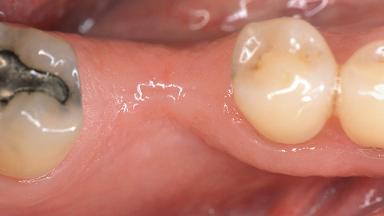

Soft-Tissue Volume Augmentation Using a Connective-Tissue Graft Harvested from the Maxillary Tuberosity

| Jaw | Mandible |

| Area | Posterior |

| # of Teeth | 1 |

| # of Implants | 1 |

| Soft Tissue Grafting | Simultaneous |